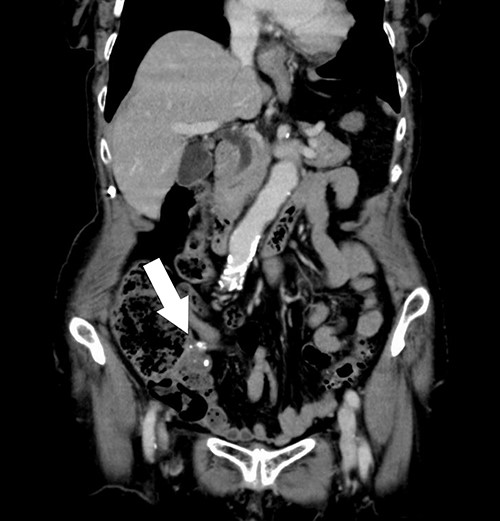

A 74-year-old female with hypertension, hyperlipidemia and hyperuricemia had a colonoscopy as a screening examination. The colonoscopy revealed an extrinsic compression with ulceration located at the cecum (Fig. 1). A multidetector computed tomography (CT) identified a low-attenuation distorted cystic lesion with focal calcification in the anatomic region of the right iliac fossa, measuring 6.1 × 5.0 × 3.7 cm (Fig. 2). Findings from the routine laboratory examinations were unremarkable, and all tumor markers were within normal range. The patient was scheduled for ileocecal resection with lymph node dissection due to the possibility of malignancy, such as appendiceal mucinous adenocarcinoma, because of the large and distorted tumor. Contrast-enhanced CT was conducted for further assessment of the findings, and we found that the cystic lesion was dramatically shrinking. It seemed improbable that rupture of the tumor had happened since no findings implied the spread of mucinous components, such as ascites or mucinous peritoneal nodules on CT. It was considered that the mucinous content was spontaneously drained from the root of the appendix to the cecum. However, the enhanced and distorted lesion with focal calcification, suggesting malignancy, had remained in concordance with the base of appendix (2.7 × 2.1 × 1.9 cm) (Fig. 3). Therefore, ileocecal resection was performed as planned, and laparoscopic procedure was selected due to the unlikelihood of the tumor rupturing. The base of appendix was distended and there were no obvious peritoneal anomalies upon visualization of the abdomen (Fig. 4). The specimen was handled with care and there was no spillage of cystic contents. The post-operative course was uneventful, and the patient was discharged on post-operative day 8.

Abdominal CT showing a cystic lesion with some calcification in the right iliac fossa (arrow).